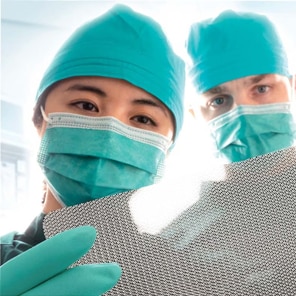

Fully resorbable implant for soft tissue reconstruction.